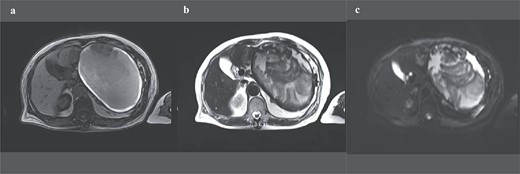

A 74-year-old Asian woman had been treated for diabetes mellitus but had stopped treatment on her own. The HbA1c level increased sharply to 16%. Blood samples showed no abnormal findings such as elevated levels of tumor markers (Table 1). There was no history of abdominal imaging, sudden abdominal pain, abdominal trauma, or abdominal surgery. Contrast-enhanced abdominal computed tomography (CT) revealed a large hematoma-like cystic lesion in the pancreatic tail (Fig. 1a–c). Calcification of the wall and internal septum was prominent. Magnetic resonance imaging (MRI) demonstrated a 156 × 112 mm marginal T1W high signal (Fig. 2a) and an internal T2W uneven low signal (Fig. 2b) on the dorsal side of the stomach, suggesting a hematoma-like cystic lesion. Diffusion showed a high signal intensity, but abnormal enhancement was not observed (Fig. 2c). Considering the possibility of intra-abdominal dissemination of the cystic tumor via a puncture, the patient underwent distal pancreatectomy and splenectomy with lymph node dissection for diagnostic and therapeutic purposes. The cyst wall adhered strongly to the surrounding tissue (Fig. 3); however, no adverse events were noted during the operation. The operating time was 7 h 19 min, and blood loss was 809 ml. The patient was discharged 11 days postoperatively, with a good postoperative course.

Preoperative abdominal enhanced MRI showing a 156 × 112 mm marginal T1W high (a) and an internal T2W uneven low signal (b); diffusion shows some high signal, but abnormal enhancement cannot be noted (c).